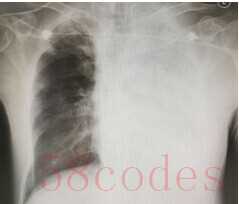

发热一天,左肺变白,紧急收治ICU

半月前,李大伯因为发热1天到浙江省立同德医院就诊,当时主要表现为发热,轻微气急,做了肺部CT,提示左肺有大片的炎症。但初始的治疗似乎并没有有效阻止病情的进展,李大伯高热不退,气更急了,自己觉得透不过气来,24小时不到再次复查胸片,结果让人大吃一惊,左边肺部基本全白。因此,李大伯被紧急收治到ICU。

图为李大伯的胸片